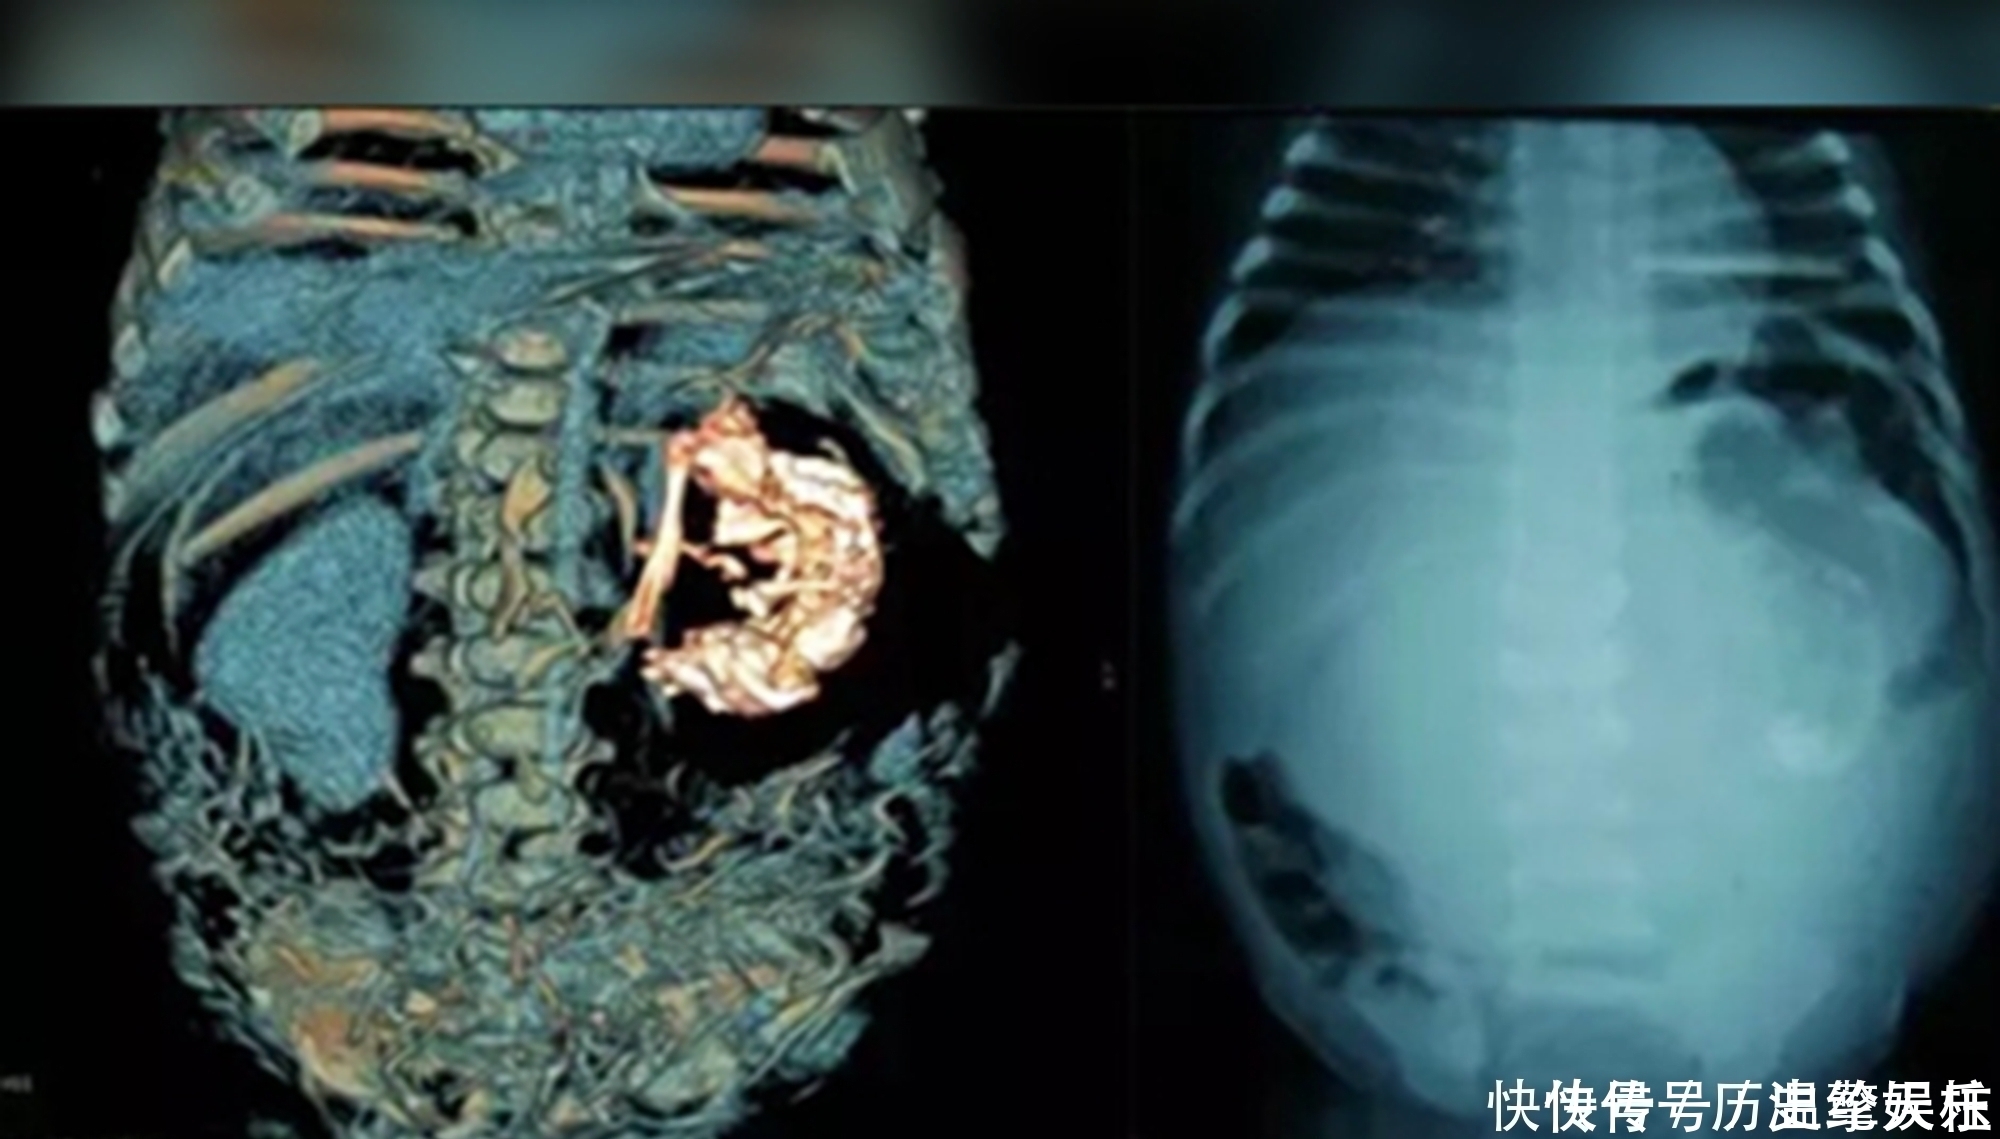

父母带梅迪纳去了镇上的医院后,主治医生起初以为是肿瘤,经过X光检查和验血,诊断结果出来后,却得到了一个令人震惊的结果——梅迪纳怀孕了!当时不过5岁六个月的梅迪纳,居然有了7个月的身孕。

因生育年龄实在太小,众人纷纷猜测是“寄生胎”,却被医生否认

不到六岁就生孩子?放在现在都算是奇闻,这个年纪的孩子本该在上幼儿园,大众认知中的人体生理构造,也让人很难相信,这名男婴是梅迪纳孕育的,纷纷提出猜测,而呼声最高的便是“寄生胎”。

这一说法并非空穴来风,新闻报道中那些小女孩甚至是小男孩,生孩子的稀奇案例,大多都是“寄生胎”在作祟,而这其实并不是真正意义上的“生孩子”,在医学上归属于连体婴的一种。

文章插图

说白了就是,孕妈怀了双胞胎后,因某种特殊原因一个胚胎将另一个胚胎“纳入其中”,这样的寄生胎,有的并不影响存活下来的那个宝宝的生长发育,甚至能在其体内寄生几十年都不被发现,这种病变,在新生儿中出现的概率约为50万分之一。